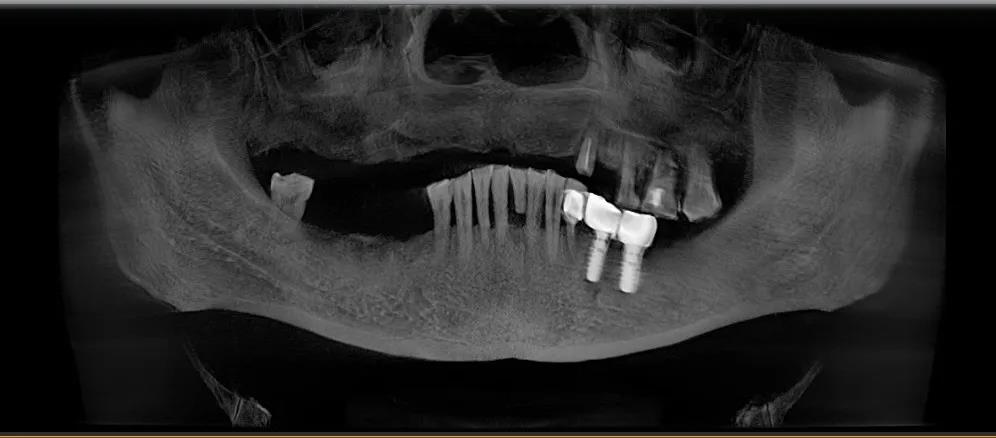

于是2017年底,经过四处寻医,我在天津一个诊所种了我的牙。

那时候因为年龄偏大,加上技术发展没有到,不能在上颌种植满口牙,只能在左下颌种了两颗新牙,正好对着左上颌残存的四颗老牙。

种牙后,效果还好,能够用左边牙齿咀嚼了。但是,一年后左上颌的四颗为我服务八十年的老牙又不争气了,牙周炎不时发作,牙根疼痛,牙体晃动,只能再改为半流食。